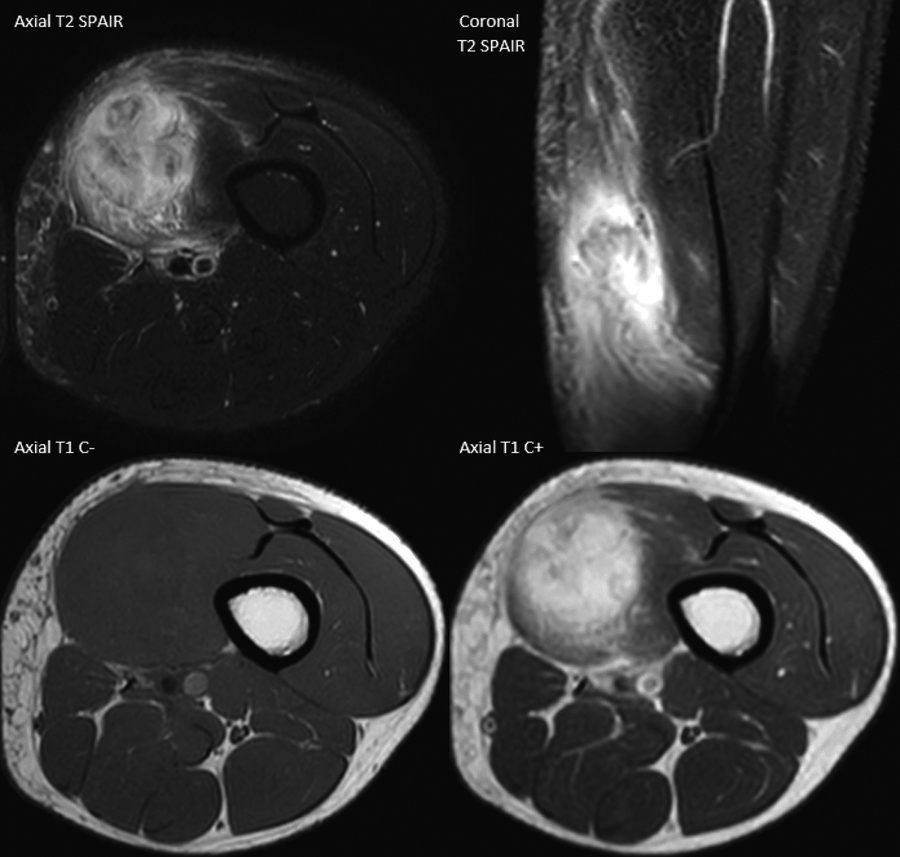

The MRI showed a vividly enhancing, T1-hypointense and T2-hyperintense, lobulated mass in the distal vastus medialis oblique muscle without restricted diffusion. There was extensive oedema between the surrounding muscle fibres and in the subcutis. No extramuscular extension or bone involvement was seen (Figure 2).

Figure 2

MRI of myositis ossificans shows marked muscle oedema and contrast enhancement.